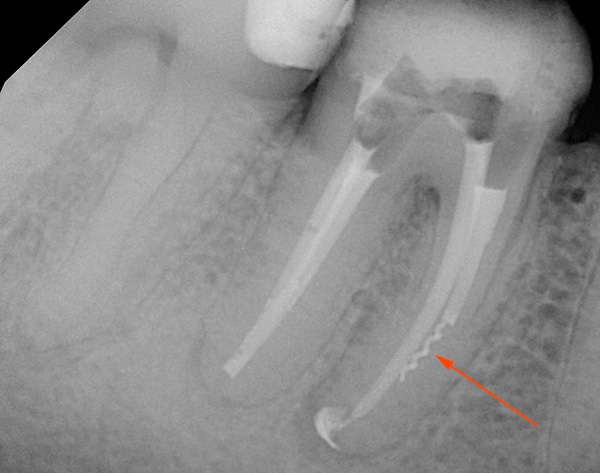

La foto sotto mostra il dente estratto con le cisti sulle radici:

nota

Parodontite periodontite - discordia. Nelle forme acute (specialmente nella fase sierosa), così come nella parodontite fibrosa e granulosa cronica, la capacità di salvare un dente del giudizio è significativamente più elevata rispetto alla parodontite granulomatosa. In generale, le parole "granuloma", "cistogranuloma" e "cisti" dovrebbero avvertirti che il trattamento potrebbe non avere successo, o il medico suggerirà immediatamente di rimuovere il dente del giudizio e questa sarà quasi sempre una decisione giustificata.